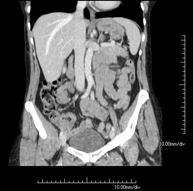

- Abdominal and pelvic CT

Diagnostic test that consists of obtaining high-definition anatomical images (bone structures, vascular structures, liver, pancreas, gallbladder, kidneys, adrenal glands, spleen, small and large intestine, bladder, uterus and ovaries, prostate and seminal vesicles, ureters, etc.) using CT (computed tomography) equipment. Most studies require the use of iodinated contrast.